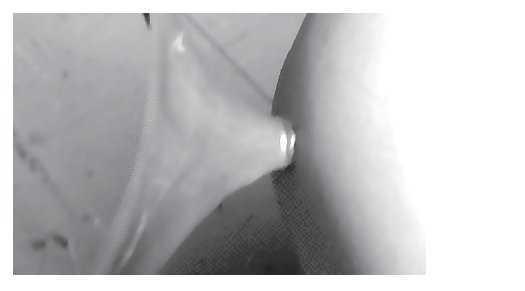

Con el fin de confirmar nuestra hipótesis, implementamos un modelo experimental, para lo cual colocamos un fragmento aislado de intestino delgado de cerdo en un bastidor de madera e introdujimos el botón metálico. Una vez dentro, acercamos una lámina metálica a 30 cm de distancia y para nuestra sorpresa, de inmediato y de manera casi violenta el dispositivo se adhirió al metal (Imagen 3). Seis horas después había causado necrosis y rotura del borde antimesentérico del segmento de intestino del animal (Imagen 4). Sabemos de las limitaciones de este modelo, pero nos permite inferir que muy probablemente la fuerza magnética del botón y la atracción del marco metálico que rodeó el espacio vital de la paciente, contribuyeron para que el fenómeno se presentara. Consideramos finalmente, que dada la difusión regional, nacional y mundial de los teléfonos celulares, no será extraño encontrar fenómenos como éste, en el cual coincidiendo tantos factores, culminaría con una complicación tan grave como la que sufrió esta menor.

Imagen 3. Se muestra el dispositivo imantado colocado en el interior del intestino del cerdo. Nótese la fuerza como se adhiere a la superficie metálica.